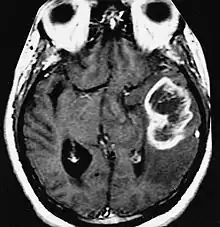

| An example of a ring-enhancement around a lesion in gliobastoma. In tumefactive multiple sclerosis, the ring-enhancement is open, not forming a complete ring. |

These atypical lesion characteristics include a large intracranial lesion of size greater than 2.0 cm with a mass effect, edema and an open ring enhancement. A mass effect is the effect of a mass on its surroundings, for example, exerting pressure on the surrounding brain matter. Edema is the build-up of fluid within the brain tissue. Usually, the ring enhancement is directed toward the cortical surface.[2] The tumefactive lesion may mimic a malignant glioma or cerebral abscess causing complications during the diagnosis of tumefactive MS. T2-hypointense rim and incomplete ring enhancement of the lesions on post-gadolinium T1- weighted imaging on brain MRI enable accurate diagnosis of TDL[3]

Diagnosis of tumefactive MS is commonly carried out using magnetic resonance imaging (MRI) and proton MR spectroscopy (H-MRS). Diagnosis is difficult as tumefactive MS may mimic the clinical and MRI characteristics of a glioma or a cerebral abscess. However, as compared to tumors and abscesses, tumefactive lesions have an open-ring enhancement as opposed to a complete ring enhancement.[1] Even with this information, multiple imaging technologies have to be used together with biochemical tests for accurate diagnosis of tumefactive MS.[36]

Magnetic resonance imaging

MRI diagnosis is based on lesions that are disseminated in time and space, meaning that there are multiple episodes and consisting of more than one area.[39] There are two kinds of MRI used in the diagnosis of tumefactive MS, T1-weighted imaging and T2-weighted imaging. Using T1-weighted imaging, the lesions are displayed with low signal intensity, meaning that the lesions appear darker than the rest of the brain. Using T2-weighted imaging, the lesions appear with high signal intensity, meaning that the lesions appear white and brighter than the rest of the brain. When T1-weighted imaging is contrast-enhanced through the addition of gadolinium, the open ring enhancement can be viewed as a white ring around the lesion.[40] A more specific MRI, Fluid attenuation inversion recovery (FLAIR) MRI show the signal intensity of the brain. Subjects with tumefactive multiple sclerosis may see a reduction of diffusion of the white matter in the affected area of the brain.[11]